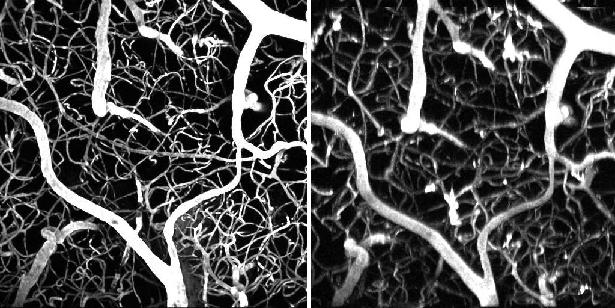

The researchers tested the efficacy of this approach on a mouse model. They started by injecting a conventional marker dye and using a femtosecond laser to map the vasculature of a section of the mouse's brain. They then switched to a laser that was a million times weaker and mapped the same region again, predictably producing no fluorescence. Finally, they kept the same weak laser but injected the dendrimer-coated nanoparticles, which allowed the researchers to produce the same imagery as in the first trial.

"This means we did the same experiment as the femtosecond laser but with one that costs hundreds of thousands of dollars less," Vinogradov said. This experiment was the first demonstration of use of lanthanide nanoparticles in neuromiaging as well as the first example of two-photon in vivo microscopy with simple, inexpensive lasers.